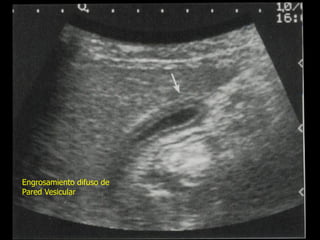

Engrosamiento difuso de

Pared Vesicular